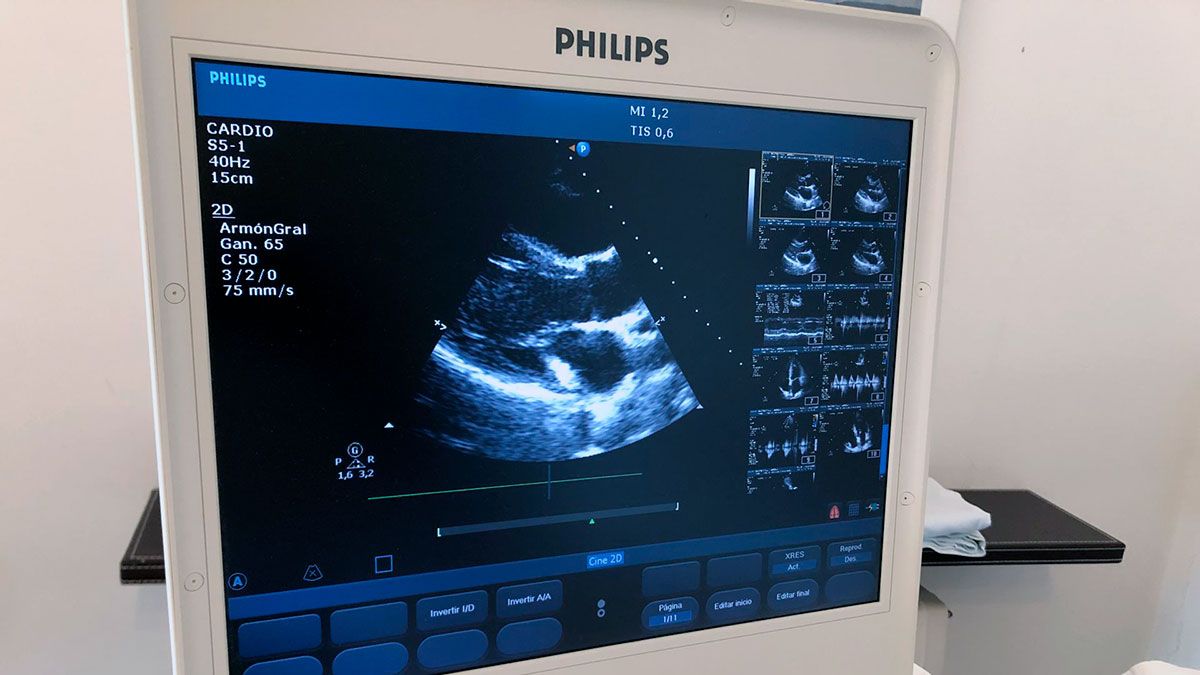

La ecocardiografía también es una exploración incruenta, es decir: no es agresiva ni hace daño. Consiste en una prueba diagnóstica cardiológica por la que, a través de una sonda de ultrasonidos aplicada sobre el tórax, podemos obtener imágenes del corazón en movimiento: de su forma, de su capacidad, de la función de sus válvulas, etc.

Es una exploración con una gran capacidad diagnóstica y pronóstica para muchas enfermedades del corazón.

Un ecocardiograma normal permite descartar una gran mayoría de enfermedades cardíacas. Además del propio estudio del corazón, permite obtener información del del funcionamiento de la circulación pulmonar y sus presiones.

El ecocardiograma es útil para saber la fuerza de contracción del músculo cardíaco, tanto en personas sanas como en aquellas que han sufrido un infarto de miocardio.

Permite estudiar todas las válvulas del corazón, identificar insuficiencias cardíacas, miocardiopatías, arritmias, endocarditis (infecciones valvulares), embolismos, así como diagnosticar y evaluar cardiopatías congénitas.